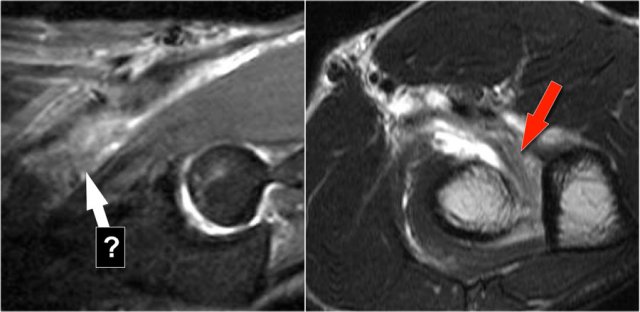

Radiobicipital bursitis

Here are sagittal and axial images of a patient who was referred to an orthopedic oncology surgeon for a mass near the elbow.

There is a partial tear (arrow) of the biceps tendon, but the question is, what is the structure that we are looking at and what is within it.

The structure is the radiobicipital bursa, so this is a bursitis.

Remember that the biceps tendon does not have a tendon sheaht, so tenosynovitis is not a possibility.

The differential diagnosis for the low intensity structures within the bursa is: synovial chondromatosis, PVNS and rice bodies.

It turned out to be rice bodies.

In any synovial lined joint or bursa these rice bodies can be formed as a result of chronic inflammation with synovial hypertrophy.

The villi will outgrow their blood supply, become necrotic and fall into the joint or bursa.

They are called rice bodies because when you open up the joint, they just look like rice.

Here another case.

The white arrow in the left sided image is pointing to the bursa.

Notice that the biceps is intact.

Next to the radiobicipital bursa (yellow arrow), also an interosseous bursa (red arrow) was described by Abdalla Skaf in Radiology in the article entitled: Bicipitoradial Bursitis: MR Imaging Findings.

Sometimes these masses mimic a tumor or they can cause impingement on the radial nerve when they become very large.